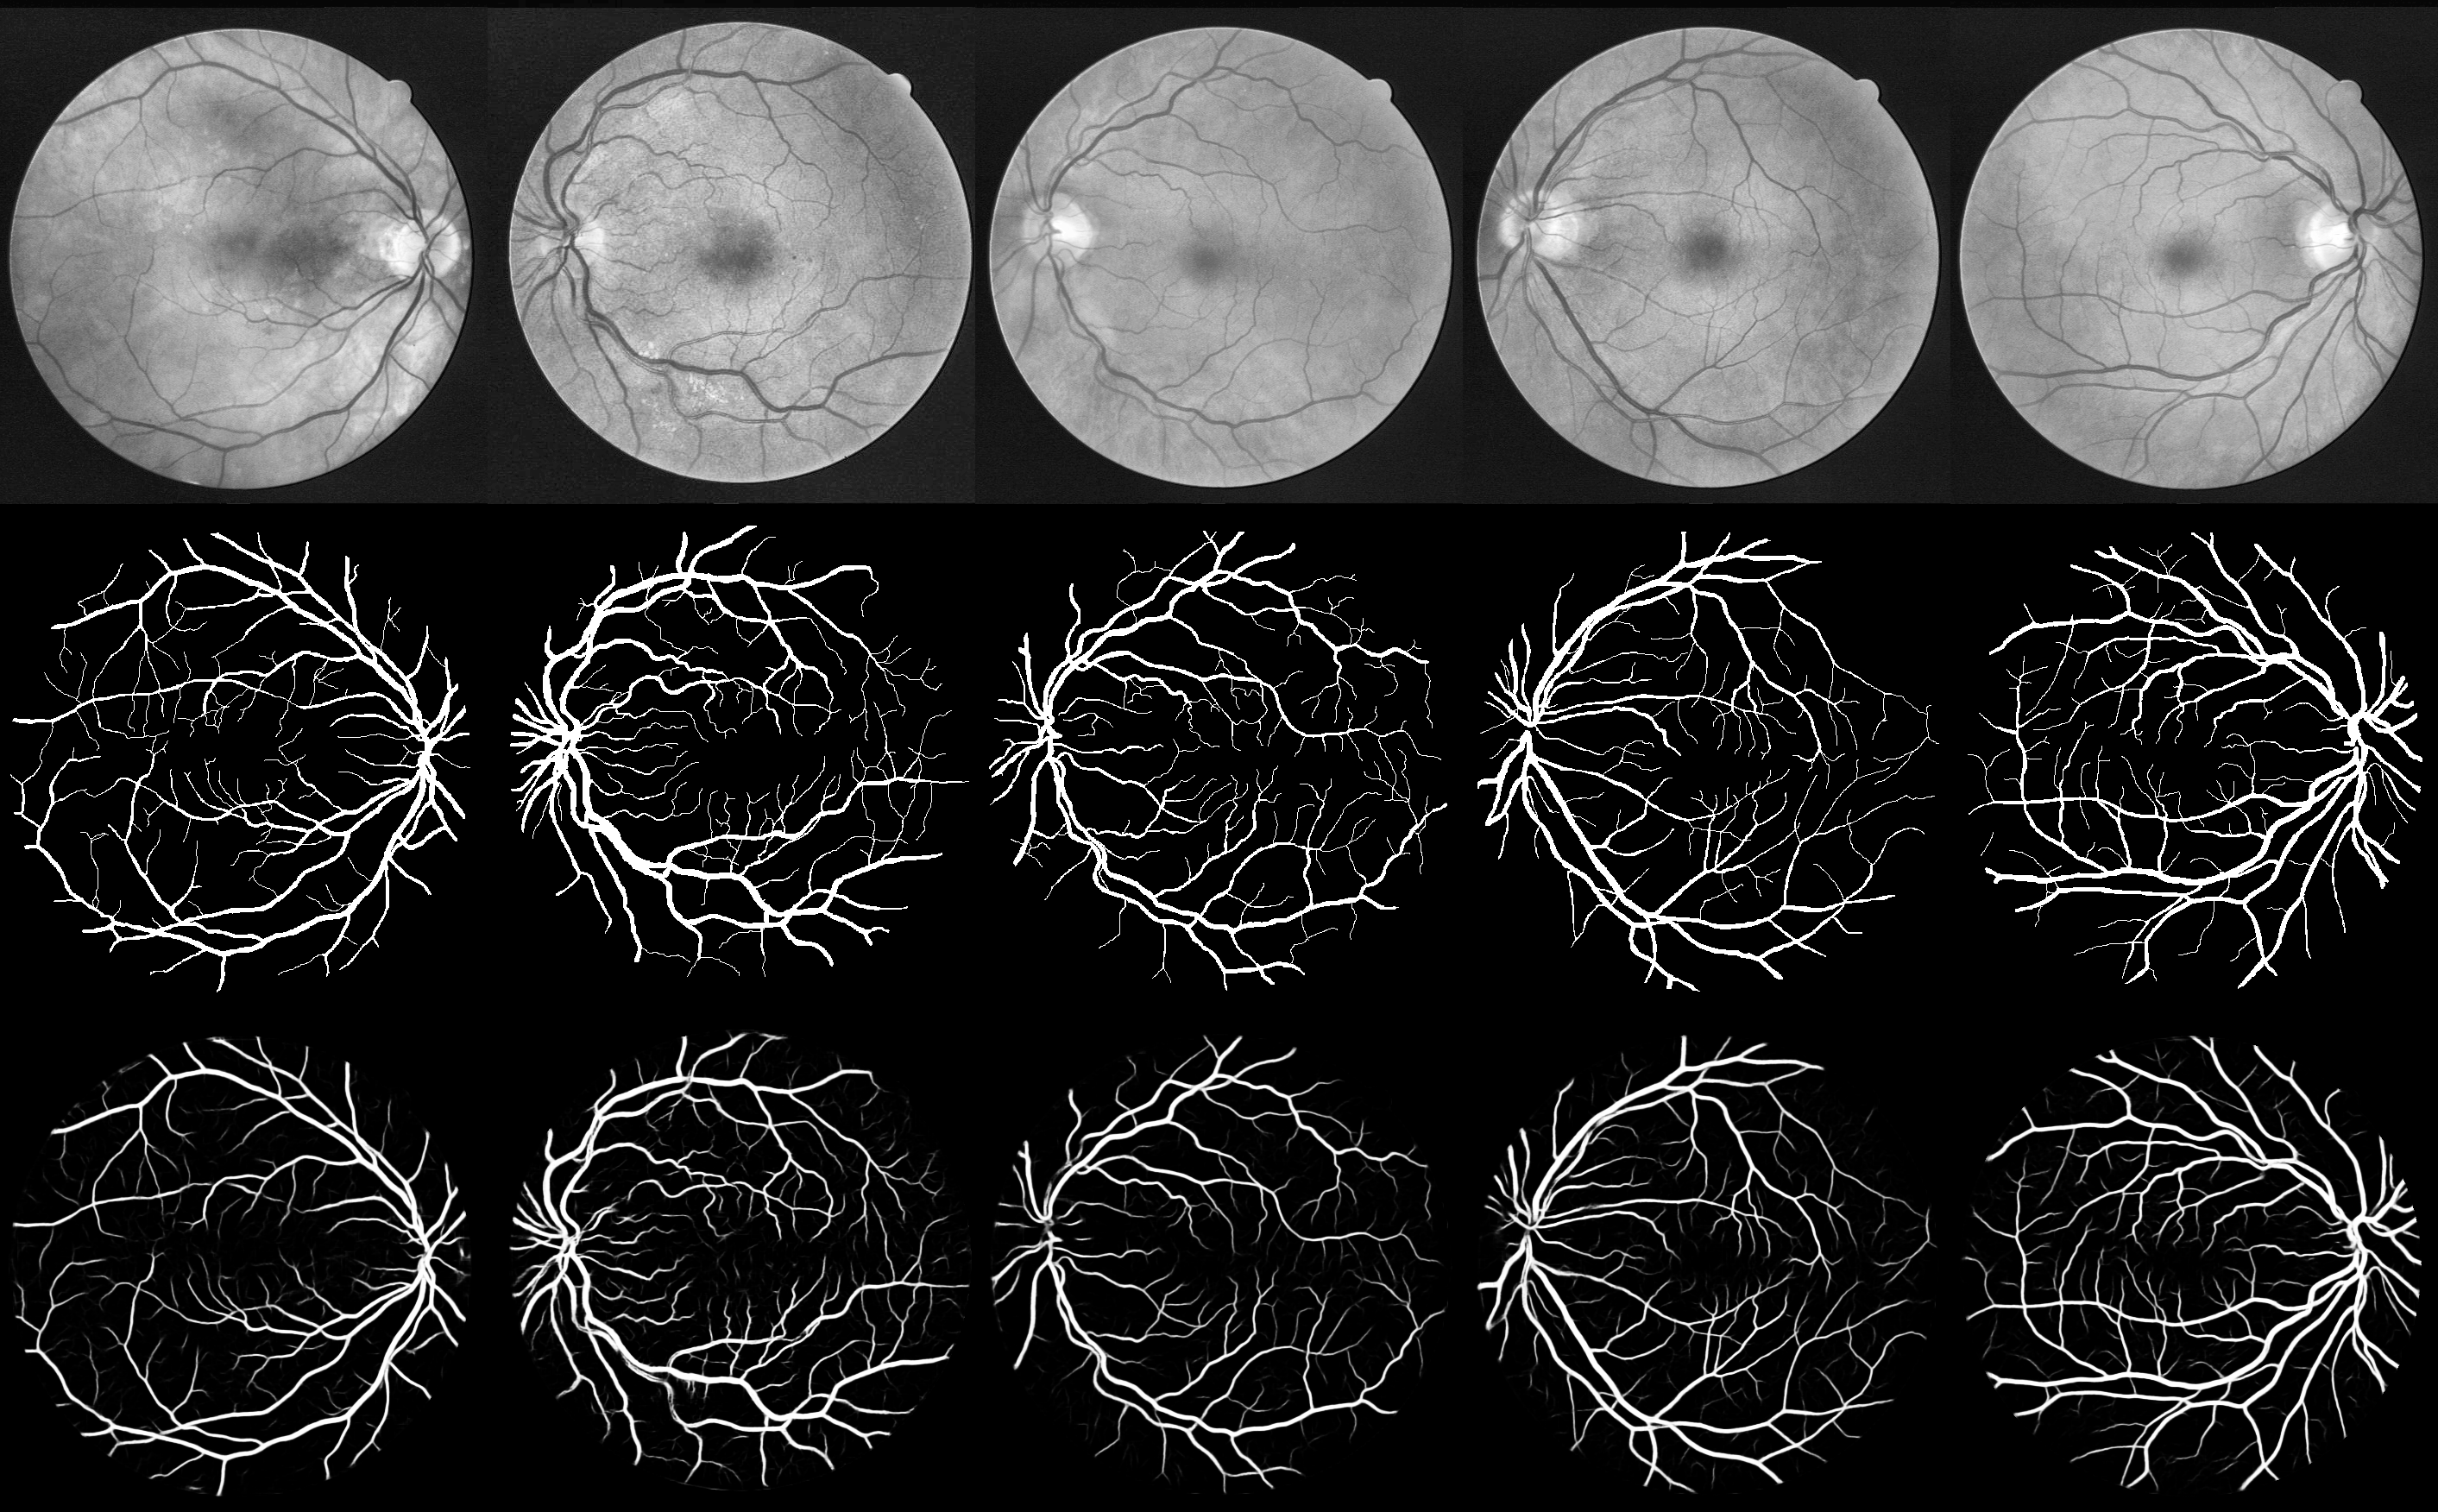

DRIVE数据库上的结果

测试使用DRIVE测试数据集中的20张图像,并以金标准作为真实标签。仅考虑属于视野(FOV)范围内的像素。视野区域由DRIVE数据库附带的掩码标识。

为了提升性能,每个像素的血管概率是通过对多次预测结果取平均值获得的。在每张测试图像中,按高度和宽度方向每隔5个像素提取一组连续且部分重叠的补丁。随后,对于每个像素,其血管概率即为覆盖该像素的所有预测补丁中概率的平均值。

./test文件夹中报告的结果对应于验证损失最小的已训练模型。该文件夹包含:

performances.txt测试结果摘要,包括混淆矩阵Precision_recall.png精确率-召回率曲线及其对应的AUC值ROC.pngROC曲线及其对应的AUC值all_*.pngDRIVE测试数据集的20张预处理后的原始图像、真实标签及预测结果sample_input_*.png预处理后训练图像的40个补丁样本及其对应的真实标签test_Original_GroundTruth_Prediction*.png从上至下依次为预处理后的原始图像、真实标签和预测结果。在预测图像中,每个像素显示的是预测的血管概率,未应用任何阈值。